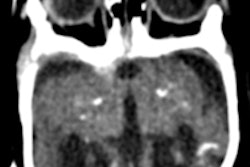

Finally, visit our CT Community for a case report by Brazilian researchers who used CT to investigate brain anomalies caused by the Zika virus in infants with congenital microcephaly. You'll also find an article in the community about a clinical trial in Scotland that evaluated the impact of coronary CT angiography on patients with chest pain.